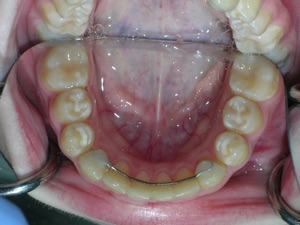

Here’s a fascinating case of a young lady who had a completely blocked out premolar.

With a combination of braces, expansion and trimming we were able to bring it in. Watch!

Here are the results.